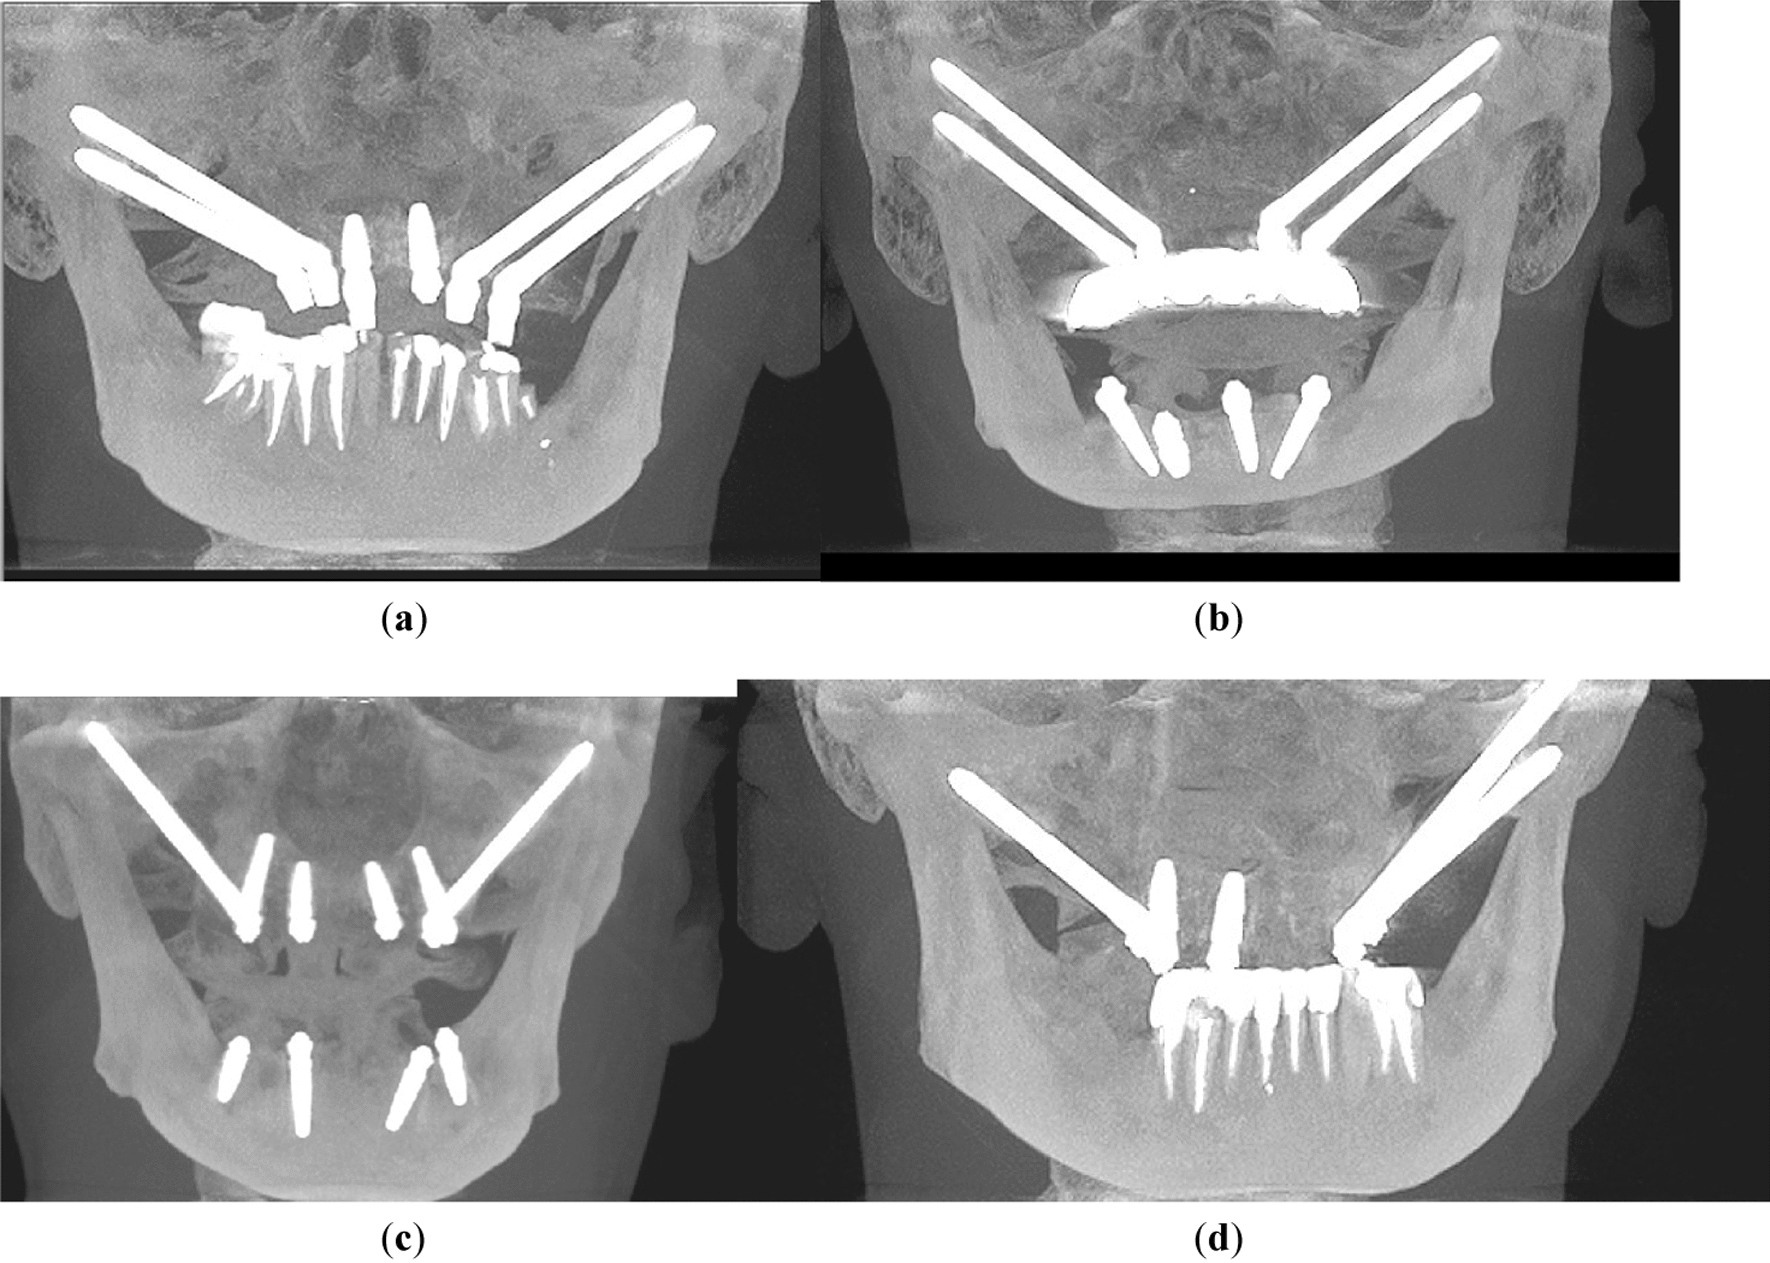

Patients were divided into four groups with varying zygomatic implant configurations. Allocation to the group was performed on the basis of bone amount. When possible, additional bone root implants were inserted for the patient. When there was not enough bone on alveolar process, zygomatic implants were inserted. Group 1 (14 patients) received four zygomatic implants plus one or two conventional implants; In group 2 (15 patients) only four zygomatic implants have been inserted; group 3 (46 patients) had two zygomatic implants plus four conventional implants, and group 4 (6 patients) received three zygomatic implants plus one or two conventional implants (Table 1). In the Fig. 1 CBCT shows the groups among which authors divided patients.

Fig. 1

In the figure there are some representative CBCT photos for each group: a group 1—4 zygomatic implants + 1 or 2 conventional implants; b group 2—4 zygomatic implants; c group 3—2 zygomatic + 4 conventional implants; and d group 4—3 zygomatic + 1 or 2 conventional implants